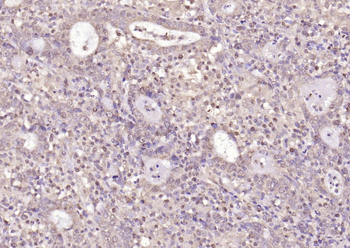

- PPM1D Rabbit Polyclonal Antibody [orb704535]Featured

IF, IHC-Fr, IHC-P

Human, Mouse, Rat

Mouse, Rat

Rabbit

Polyclonal

Unconjugated

100 μl, 50 μl, 200 μl - HSC70 Mouse Monoclonal Antibody [orb704174]Featured